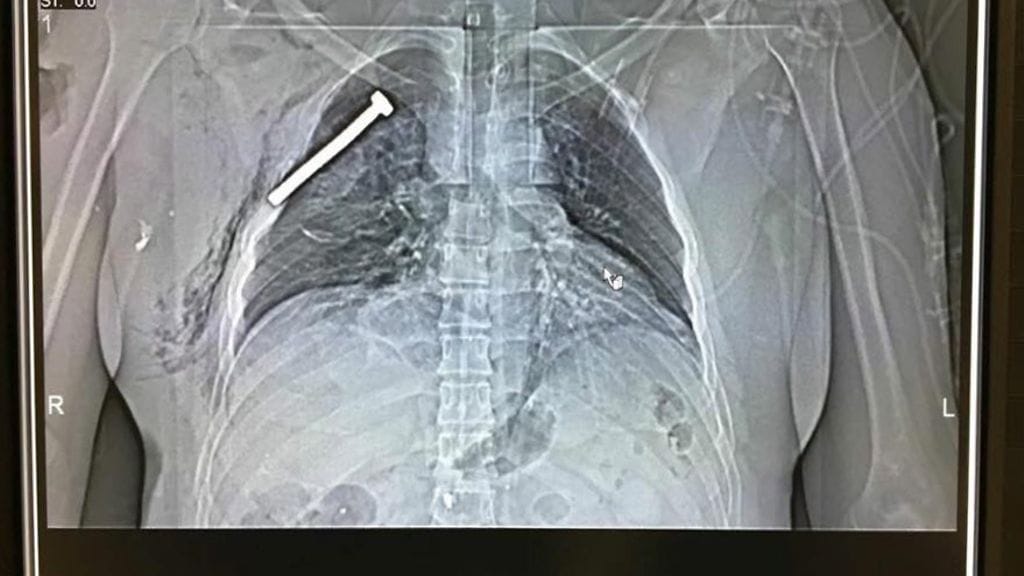

Käytetyt räjähteet olivat suurella varmuudella itsetehtyjä ja sisälsivät muun muassa runsaasti metallinpalasia, kuten nauloja ja pultteja.